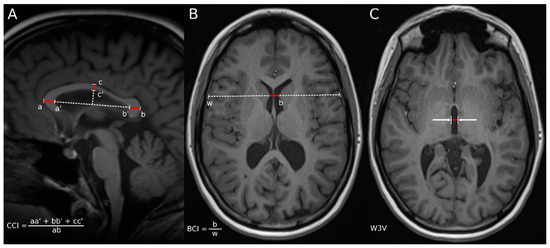

- Figueira, F.F.; Santos, V.S.; Figueira, G.M.; Silva, A.C. Corpus callosum index: A practical method for long-term follow-up in multiple sclerosis. Arq. Neuro-Psiquiatr. 2007, 65, 931–935. [Google Scholar] [CrossRef]

- Fujimori, J.; Uryu, K.; Fujihara, K.; Wattjes, M.P.; Suzuki, C.; Nakashima, I. Measurements of the corpus callosum index and fractional anisotropy of the corpus callosum and their cutoff values are useful to assess global brain volume loss in multiple sclerosis. Mult. Scler. Relat. Disord. 2020, 45, 102388. [Google Scholar] [CrossRef] [PubMed]

- Gonçalves, L.I.; Dos Passos, G.R.; Conzatti, L.P.; Burger, J.L.P.; Tomasi, G.H.; Zandoná, M.É.; Azambuja, L.S.; Gomes, I.; Franco, A.; Sato, D.K.; et al. Correlation between the corpus callosum index and brain atrophy, lesion load, and cognitive dysfunction in multiple sclerosis. Mult. Scler. Relat. Disord. 2018, 20, 154–158. [Google Scholar] [CrossRef]

- Bermel, R.A.; Bakshi, R.; Tjoa, C.; Puli, S.R.; Jacobs, L. Bicaudate ratio as a magnetic resonance imaging marker of brain atrophy in multiple sclerosis. Arch. Neurol. 2002, 59, 275–280. [Google Scholar] [CrossRef]

- Bermel, R.A.; Bakshi, R. The measurement and clinical relevance of brain atrophy in multiple sclerosis. Lancet Neurol. 2006, 5, 158–170. [Google Scholar] [CrossRef]

- Granberg, T.; Bergendal, G.; Shams, S.; Aspelin, P.; Kristoffersen-Wiberg, M.; Fredrikson, S.; Martola, J. MRI-Defined Corpus Callosal Atrophy in Multiple Sclerosis: A Comparison of Volumetric Measurements, Corpus Callosum Area and Index. J. Neuroimaging 2015, 25, 996–1001. [Google Scholar] [CrossRef]

- Butzkueven, H.; Kolbe, S.C.; Jolley, D.J.; Brown, J.Y.; Cook, M.J.; van der Mei, I.A.; Groom, P.S.; Carey, J.; Eckholdt, J.; Rubio, J.P.; et al. Validation of linear cerebral atrophy markers in multiple sclerosis. J. Clin. Neurosci. 2008, 15, 130–137. [Google Scholar] [CrossRef] [PubMed]

- Martola, J.; Stawiarz, L.; Fredrikson, S.; Hillert, J.; Bergstrom, J.; Flodmark, O.; Aspelin, P.; Kristoffersen Wiberg, M. Rate of ventricular enlargement in multiple sclerosis: A nine-year magnetic resonance imaging follow-up study. Acta Radiol. 2008, 49, 570–579. [Google Scholar] [CrossRef] [PubMed]

- Muller, M.; Esser, R.; Kotter, K.; Voss, J.; Muller, A.; Stellmes, P. Third ventricular enlargement in early stages of multiple sclerosis is a predictor of motor and neuropsychological deficits: A crosssectional study. BMJ Open 2013, 3, e003582. [Google Scholar] [CrossRef]

- Pontillo, G.; Cocozza, S.; Di Stasi, M.; Carotenuto, A.; Paolella, C.; Cipullo, M.B.; Perillo, T.; Vola, E.A.; Russo, C.; Masullo, M.; et al. 2D linear measures of ventricular enlargement may be relevant markers of brain atrophy and long-term disability progression in multiple sclerosis. Eur. Radiol. 2020, 30, 3813–3822. [Google Scholar] [CrossRef]

- Cappelle, S.; Pareto, D.; Tintoré, M.; Vidal-Jordana, A.; Alyafeai, R.; Alberich, M.; Sastre-Garriga, J.; Auger, C.; Montalban, X.; Rovira, À. A validation study of manual atrophy measures in patients with Multiple Sclerosis. Neuroradiology 2020, 62, 955–964. [Google Scholar] [CrossRef]

- Ajitomi, S.; Fujimori, J.; Nakashima, I. Usefulness of two-dimensional measurements for the evaluation of brain volume and disability in multiple sclerosis. Mult. Scler. J. Exp. Transl. Clin. 2022, 8, 20552173211070749. [Google Scholar] [CrossRef] [PubMed]